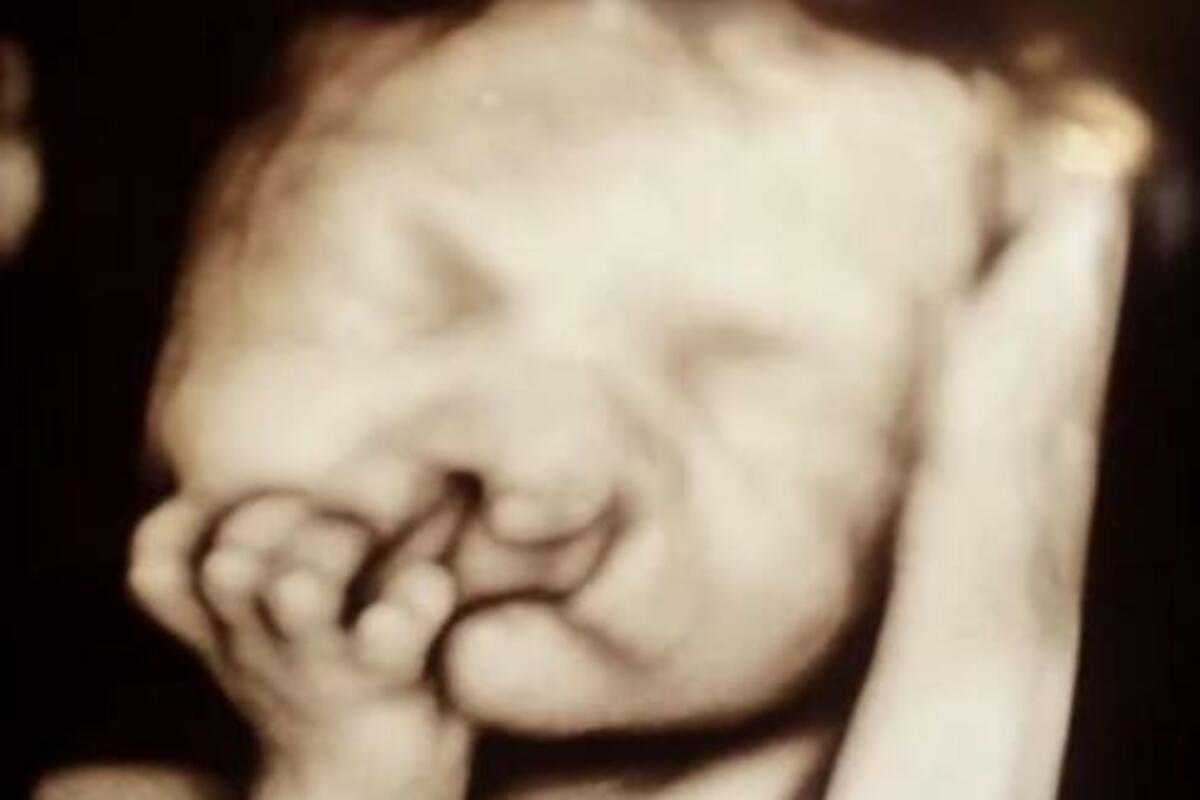

"Treba biti ponosan na svoju bebu bez obzira na okolnosti. Mi smo želeli da pokažemo da je moguće promeniti ono što su pokazali ultrazvuk, a potom i prve fotografije mog Brodija. Mislili smo da ljudima treba pokazati da je moguće da se izađe na kraj sa rascepima na licu", istakla je Sara Heler, majka malog dečaka koji se rodio sa rascepom usne i nepca.

Sindrom rascepa usne dešava se kada se određena tkiva ne formiraju kako treba, a na ultrazvuku moguće je videti ga već posle 12. nedelje trudnoće.